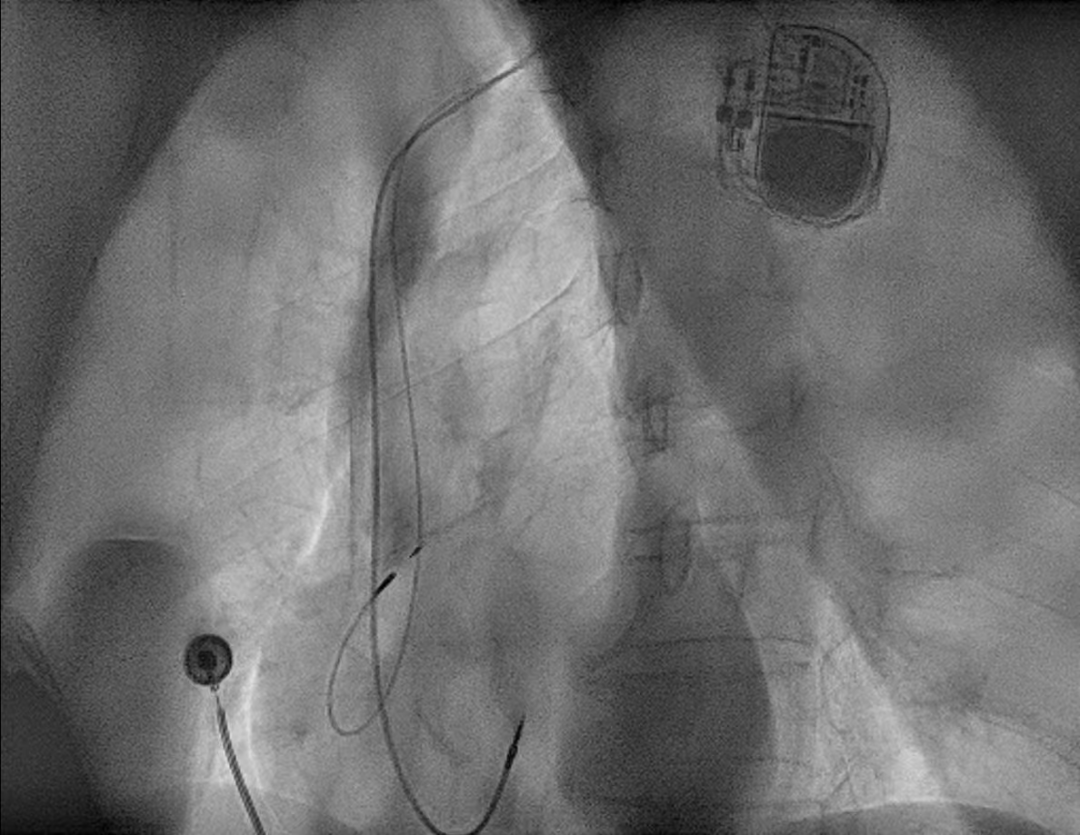

患者李军(化名)因胸痛胸闷一日入住我院CCU科,临床诊断为不稳定型心绞痛、冠状动脉性心脏病、病态窦房结综合征。经过术前讨论决定为患者在局麻下行双腔永久起搏器植入术。科室团队全面评估患者心律、心房传导与心脏结构,精准制定个体化手术方案;术中凭借丰富起搏介入经验与精细操作,顺利将电极精准定位至Bachmann束区域,完成起搏参数测试与系统植入。术后患者心律规整、双房同步性良好,恢复顺利,充分体现该术式的安全性与有效性。术后一个月程控随访显示患者起搏器参数正常,起搏功能良好。

正位 左前斜